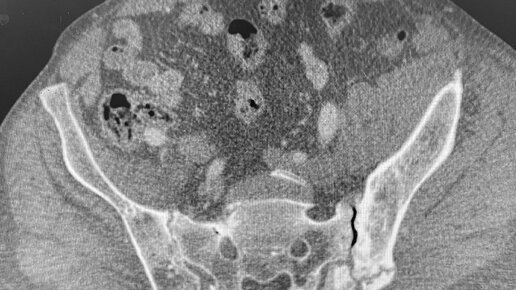

КТ таза